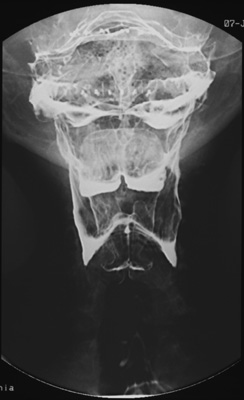

| AP view of the barium-coated pharynx and hypopharynx obtained during phonation demonstrates normal anatomy but also aspiration of barium into the larynx and trachea.